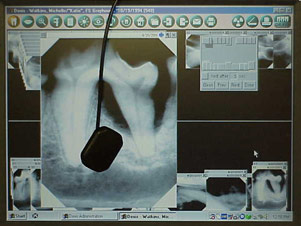

CCD/CMOS Sensor

This technique uses a sensor plate attached to a computer.

The advantage is that the image is immediately displayed on

the computer. The disadvantage is that the sensors are expensive

and, at this time, only come in periapical film size 2.

Digital radiographs and CCD/CMOS

sensor plate